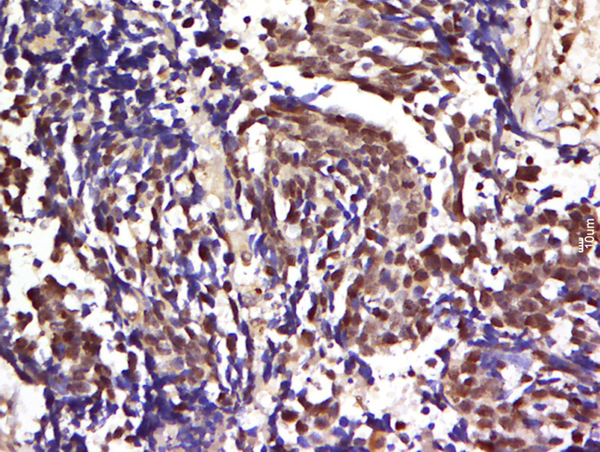

Paraformaldehyde-fixed, paraffin embedded human lung carcinoma tissue; Antigen retrieval by boiling in sodium citrate buffer(pH6) for 15min; Block endogenous peroxidase by 3% hydrogen peroxide for 30 minutes; Blocking buffer (normal goat serum) at 37°C for 20min; Antibody incubation with Rabbit Anti-CBL2 (Tyr700) Polyclonal Antibody, Unconjugated (bs-4072R) at 1:500 overnight at 4°C, followed by a conjugated secondary and DAB staining